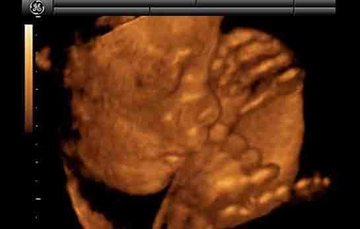

• 20. Hafta: Fetüs, yaklaşık 25 cm uzunluğundadır. Anne adayı, ultrason ile bebeğin cinsiyetini öğrenebilir.

• 21. Hafta: Fetüs, daha fazla kas ve yağ kazanmaya başlar. Anne adayı, karnındaki hareketleri daha sık hissedebilir.

• 22. Hafta: Fetüs, yaklaşık 27 cm uzunluğundadır. Anne adayı, ciltte değişiklikler yaşayabilir.